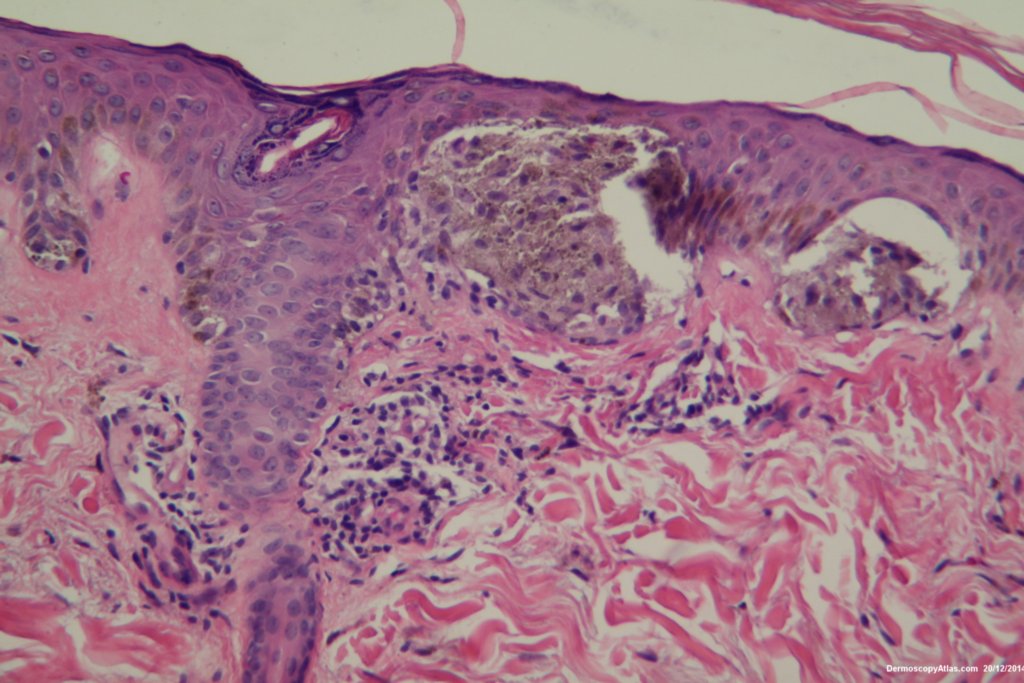

The histopathology shows nests of epitheliod and spindled cells with lots of melanin in them. There are a few melanophages in the dermis. There is no inflammatory reaction beneath this lesion. There were no mitoses. This is just a junctional lesion ie no nests of cells in the dermis.